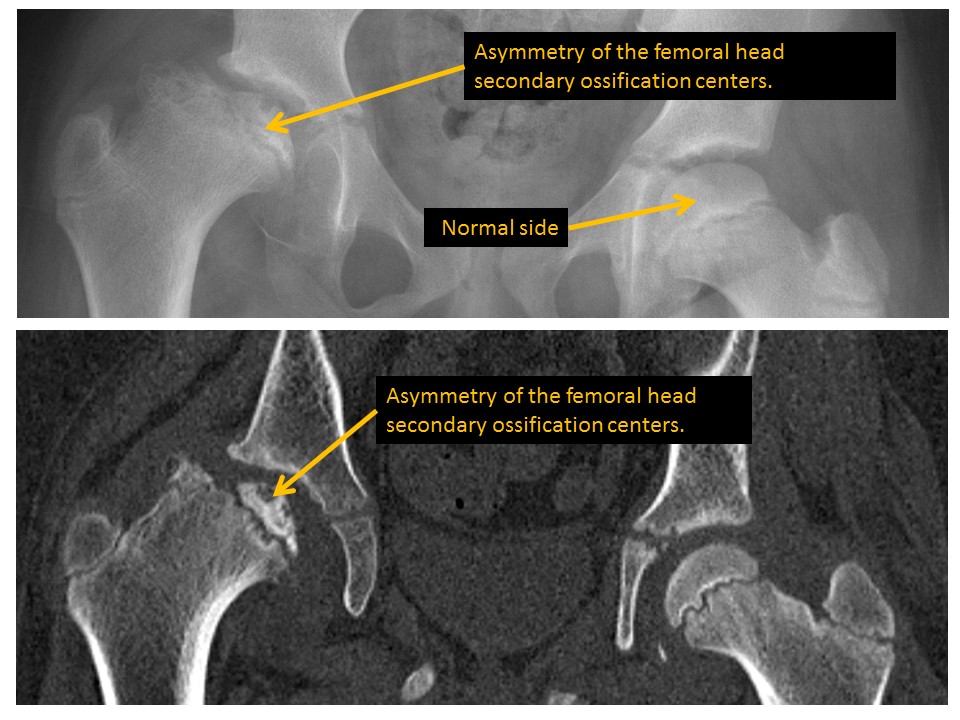

There is abnormal osseous density of the femoral epiphyseal ossification centers. [Yes/No]

Femoral epiphyseal ossification centers are asymmetric in size. [Yes/No]